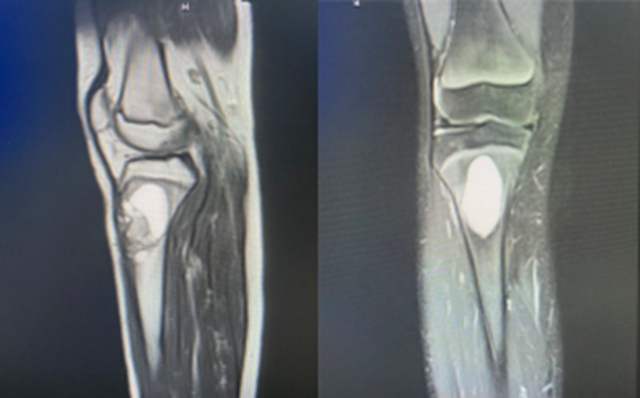

影像检查提示:小王胫骨近段偏心性皮质骨内出现了溶骨病变(骨化性纤维瘤),没想到病根竟是让人意想不到的肿瘤。

8月3日,在李森教授的指导下,由骨伤科脊柱·肿瘤一组朱凯主治医师、雷杨医师为小王完成了胫骨近端病灶清除、植骨、肢体重建手术治疗,将肿瘤彻底清除、灭活,重建原有肢体骨骼形态,手术历时2个半小时,顺利完成。